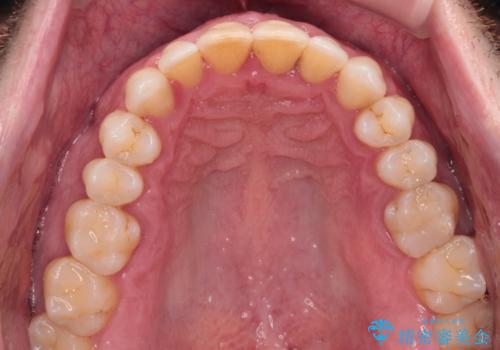

- 前歯でものを噛みきりたいとのことで来院された患者様です。

以前矯正治療を経験されたそうですが、舌の突出癖により上下前歯に隙間ができている様子でした。

前歯の非接触改善は、インビザラインの得意とするところですが、マウスピース矯正は絶対に継続できないとのことで、ワイヤー装置にて矯正治療を行うこととしました。